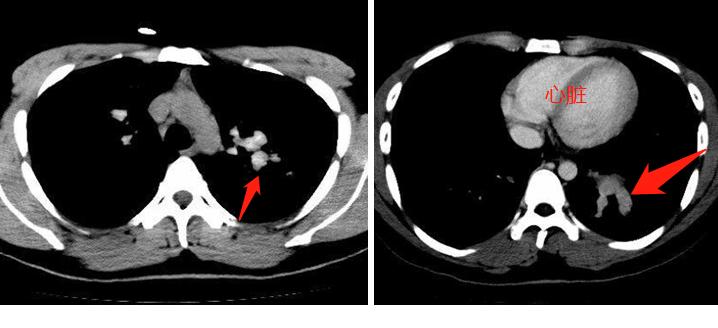

我们再接着看纵隔窗,就能明白这是什么疾病了:

从这两张纵隔窗CT片上,我们发现支气管内的充填物密度很高,偏灰白色,比胸壁肌肉密度高很多。

这种高密度的粘液栓对诊断有很高的提示意义,说明这里面存在曲霉菌感染(一种常见真菌),这种真菌能富集空气中的铁、锰离子,造成密度增加,提示诊断。这种 粘液嵌塞伴高密度,文献报道约50%的病人可以在CT片上见到。